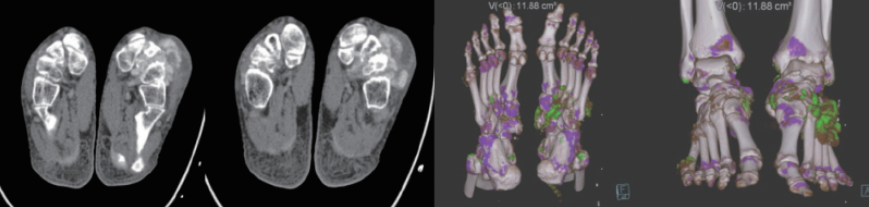

?雙能量成像技術(shù):具有定量及成分分析功能,可用于痛風石檢測,結(jié)石成分分析,骨髓顯像等;

案例圖

痛風石檢測